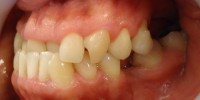

1- Foto inicial donde observamos mordida invertida anterior con importante apiñamiento y desviacion linea media dentaria 1- Foto inicial donde observamos mordida invertida anterior con importante apiñamiento y desviacion linea media dentaria Deja un comentarioLo siento, tenés que estar conectado para publicar un comentario.